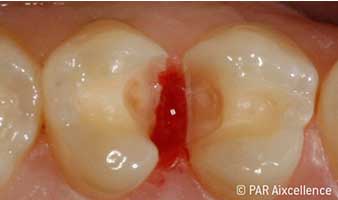

Рис. 3. При первоначальном раскрытии кариозной полости четко видны пораженные ткани